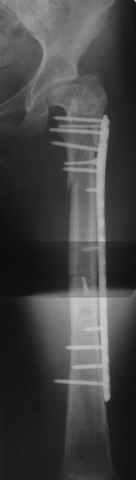

Пациентка 23 лет, доставлена в клинику с Диагнозом: Закрытый сегментарный оскольчатый перелом левой бедренной кости в верхней и средней трети. Травма в результате ДТП 10.03.2006г. Из анамнеза у пациентки диспластический левосторонний коксартроз, S-образный сколиоз 2ст. В 1999г в Кургане выполнялась остеотомия бедра в нижней трети и коррекция укорочения конечности на 3 см (рентгенограммы бедра и таза до травмы в приложении). До получения травмы пациентка ходила без боли с полной нагрузкой на левую ногу. Учитывая дисплазию левого ТБС, пациентке, вероятно, предстоит операция тотального эндопротезирования лев ТБС, что требует анатомичного восстановления проксимальногоотдела бедра. Рассматриваются следующие вариант остеосинтеза:1) Экстракортикальный остеосинтез проксимального и дистального перелома пластиной с угловой стабильностью типа LISS( г Рыбинск); 2) Ретроградный интрамедуллярный блокированный остеосинтез дистального перелома и накостный синтез проксимального пластиной с угловойстабильностью; 3) Остеосинтез бедра в аппарате внешней фиксации с фиксацией таза и возможной открытой адаптацией фрагментов. Хотелось бы узнать Ваше мнение. С уважением Украинский Евгений, г.Краснодар, ККБ N1, ТОО N3.

Уважаемые коллеги, приношу извенения за молчание. Готовили материал и боялись писать раньше времени. Все хотели убедиться в том, что после операции все будет спокойно. Спасибо за отклики и советы. К сожалению, гамма-гвоздя, штифтов с возможностью установки более 2-х блокирующих винтов у нас нет. Зато нашли достаточно длинную пластину с угловой стабильностью. После проведения предоперационной подготовки и планирования выполнили остеосинтез. В условиях рентгеноперационной, после репозиции дистрактором из одного разреза 5см в проксимальном отделе подкожно установили пластину. Пришлось выполнить дополнительный разрез до5см в проекции перелома диафиза в средней трети, из которого удалось репонировать перелом и выполнить фиксацию стягивающим винтом. Затем все завершилось наложением пластины с угловой стабильностью. Пластина оказалась достаточно длинной, что позволило перекрыть все переломы с фиксацией каждого отломка минимум 5-ю винтами. Синтез достаточно стабилен. Пациентка активизирована на 3-и сутки(снимки прилагаются). В настоящий момент пациентка выписана на амбулаторное лечение. Еще раз, огромное спасибо всем за помощь в выборе тактики и просто совете. С уважением Украинский Е.

Прошу прощения, со снимками глюк произошел. Высылаю. С уважением Евгений У.